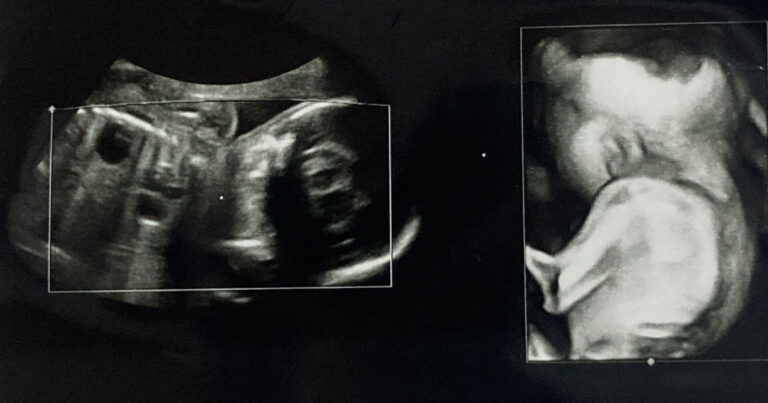

潜伏二分脊椎 (SBO) は脊椎の一般的な奇形です。これは母親の子宮内で赤ちゃんが発育する過程、通常は妊娠の最初の月に発生します。

SBO は、医師が検査を指示したり、無関係な病気の検査を行ったりしたときに、偶然にのみ検出されることがよくあります。それは、症状が無症状であることが多いためです。えくぼ、皮膚の変色、髪の毛の束などの視覚的な手がかりにより、医師は SBO を疑う可能性があります。

X線検査により、脊椎の奇形があるかどうかを判断できます。医師が索繋ぎ症候群の疑いがある場合は、MRI スキャンを指示することがあります。